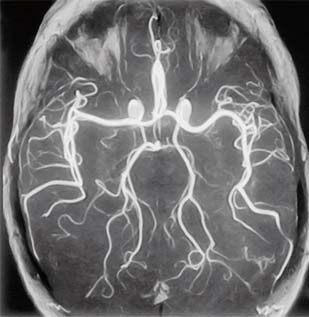

Ангиография

Врач при подозрении на тромбоз сосудов головного мозга убедится в наличии способствующих этому факторов: беременности, гнойной инфекции в области головы, длительному приему гормональных контрацептивных пилюль и др. Для диагностирования болезни применяется ангиография или ядерно-магнитный резонанс. Тромбоз вен головного мозга диагностировать сложно, даже если причина ясна, например, осложнение после операции.